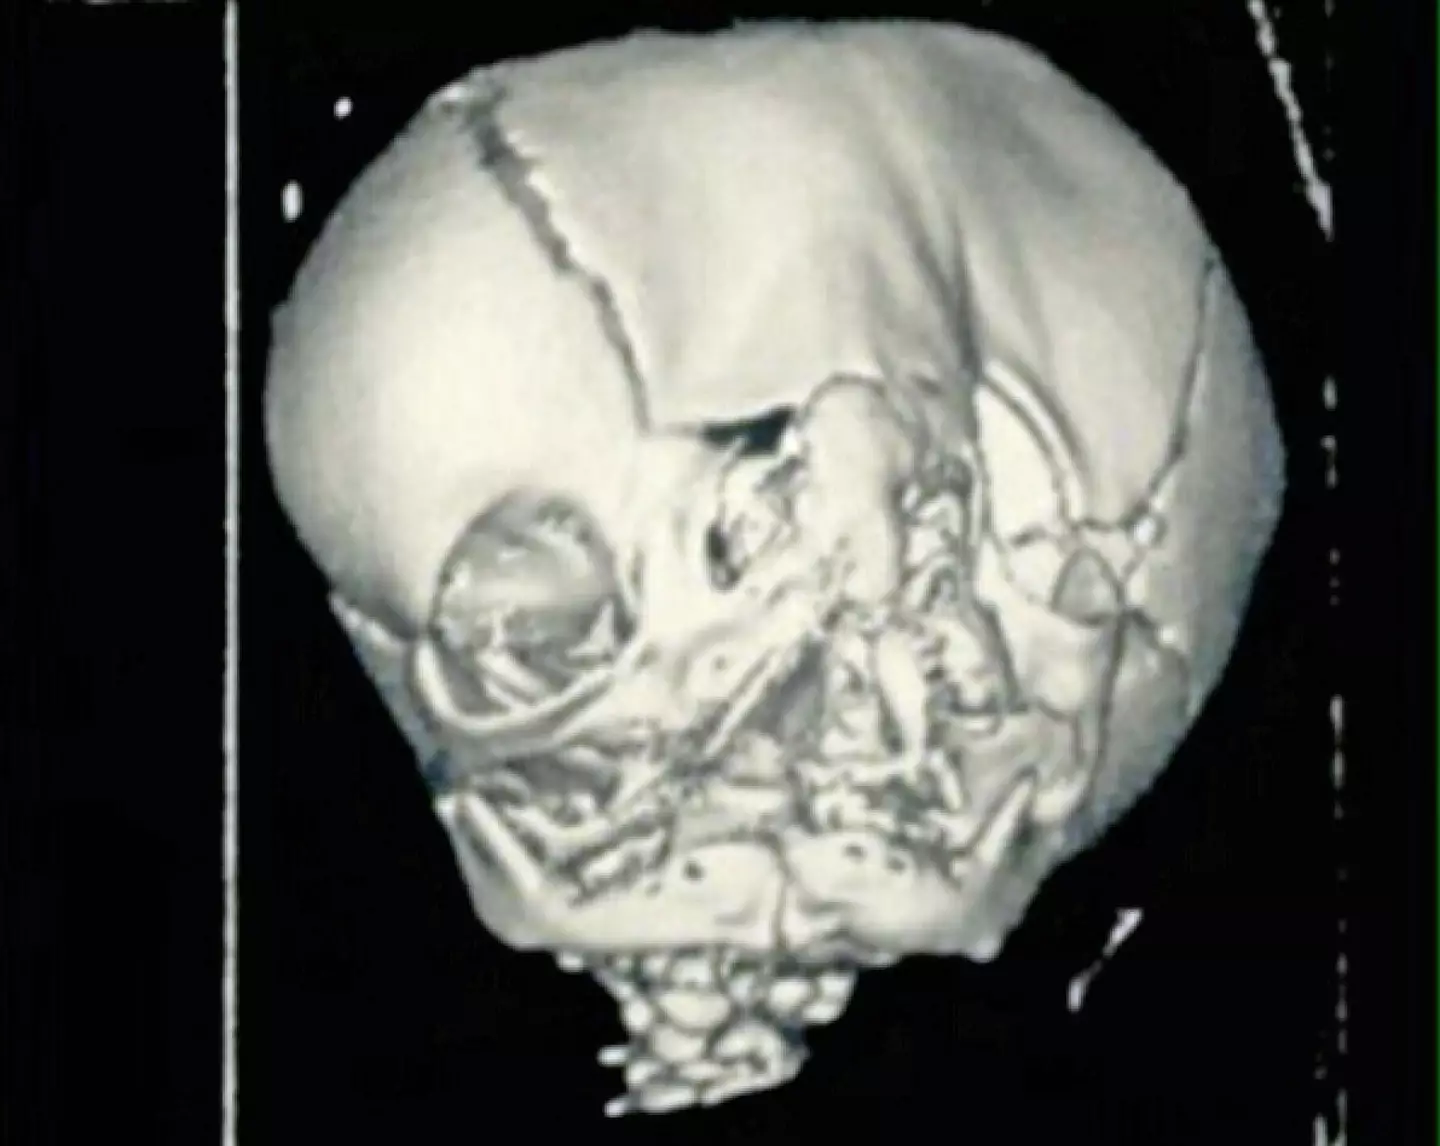

Tres Johnson, from Missouri, has what's known as craniofacial duplication, and the condition is so rare that it affects just 36 people worldwide.

It is caused by the Sonic the Hedgehog (SHH) gene which deforms the growth of the human skull and comes with a life expectancy of just ten years.

As reported by The Sun in 2017, the teenager suffers from seizures and cognitive delays and was born with a cleft, two separate nostrils, a head with an unusual, duplicate shape.

"His one eye looked like it was bulging out and the other sucked in, because his eyes are further apart he sees peripherally instead."

His physical appearance has also been altered to aid the teenager, and he has had an operation to close his cleft and reshape his skull.